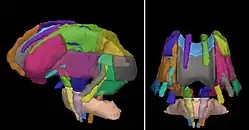

Visualization of some atlas-based ROIs which correspond to major anatomical fiber tracts. The atlas was provided as part of a download of DTI studio.

Visualization of some atlas-based ROIs which correspond to major anatomical fiber tracts. The atlas was provided as part of a download of DTI studio. -

Cortical parcellations derived from SPGR images obtained from a tumor patient.

Cortical parcellations derived from SPGR images obtained from a tumor patient. -